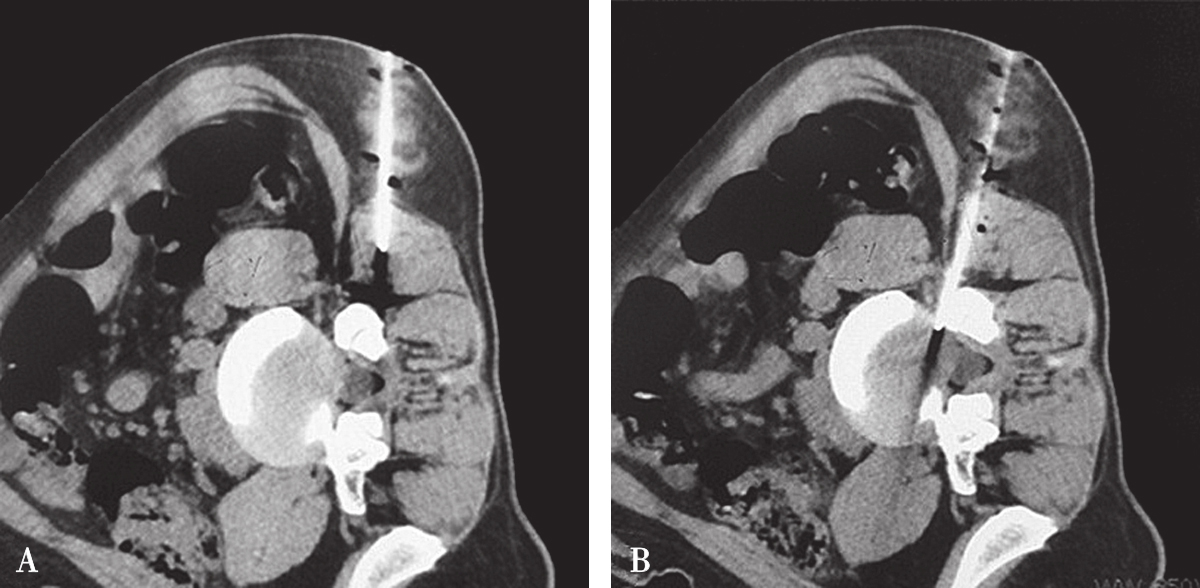

图3-3-13 L 4/5 侧方入路-不同层面横断位像

A.靶点偏头侧平面;B.靶点操作平面;C.靶点偏足侧平面